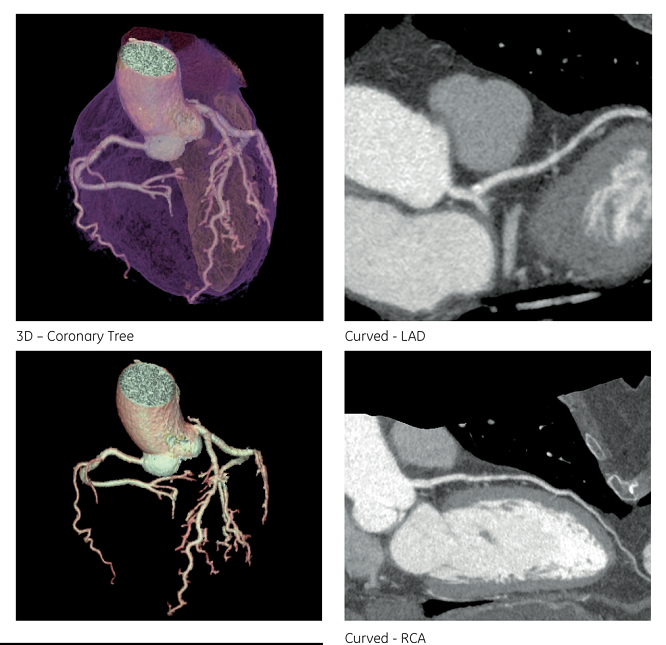

结论 该患者心率较快(屏气前心率为77 BPM,扫描时心率为69 BPM),采用80kV、单心跳舒张期采集,得到满足临床诊断的图像质量,而患者所受射线剂量仅为 0.25 mSv。(图2)。 On this patient with a relatively high heart rate & #40;77 BPMbefore apnea, 69 BPM during acquisition& #41;, the exam was performed within asingle diastolic phase, at 80 kV, enabling diagnostic quality images to beacquired at a quarter of a milliSievert.

图2: CCTA 图像

Jacques Feignoux医生的评价“单心动周期的轴位采集、新的ASiR-V迭代重建、低kV下高质量的图像,这些技术使Revolution CT可以常规应用非常低的射线剂量得到非常优秀的心脏图像。” Thanks to the one-beat axial acquisition, the newiterative reconstruction technology ASiR-V and the high image quality at low kV, Revolution CT delivers cardiac CT with excellent image quality at very low dose routinely.